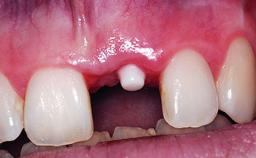

A 15-year-old male patient was referred to us by his pediatric dentist in June 2004 for evaluation of treatment options for his failing tooth 21. The patient had recently seen an endodontist for internal bleaching and been advised that there had been significant resorption and ankylosis. The patient’s mother was concerned because the tooth appeared shorter than the adjacent one. His past dental history was significant for trauma (September 2001), where the tooth had been avulsed and reimplanted. Teeth 11 and 21 had been endodontically treated.